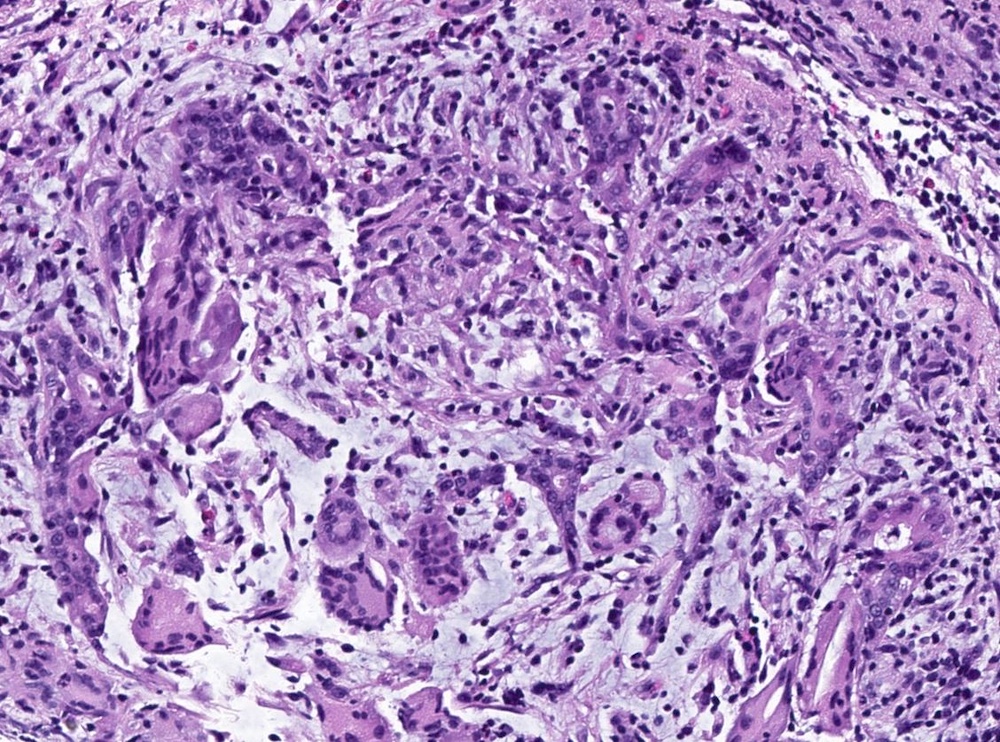

Microscopic (histologic) description

- Lobulocentric granulomatous inflammation (Pathology 2004;36:254)

- Granulomas often contain neutrophils

- Neutrophils can create microabscesses; overlapping features with cystic neutrophilic granulomatous mastitis

- Multinucleated giant cells, lymphocytes, plasma cells and eosinophils within and around lobules

- Extensive inflammation might obliterate lobulocentric distribution

- Caseous necrosis not present

- Schauman and asteroid bodies not common

Microscopic (histologic) images